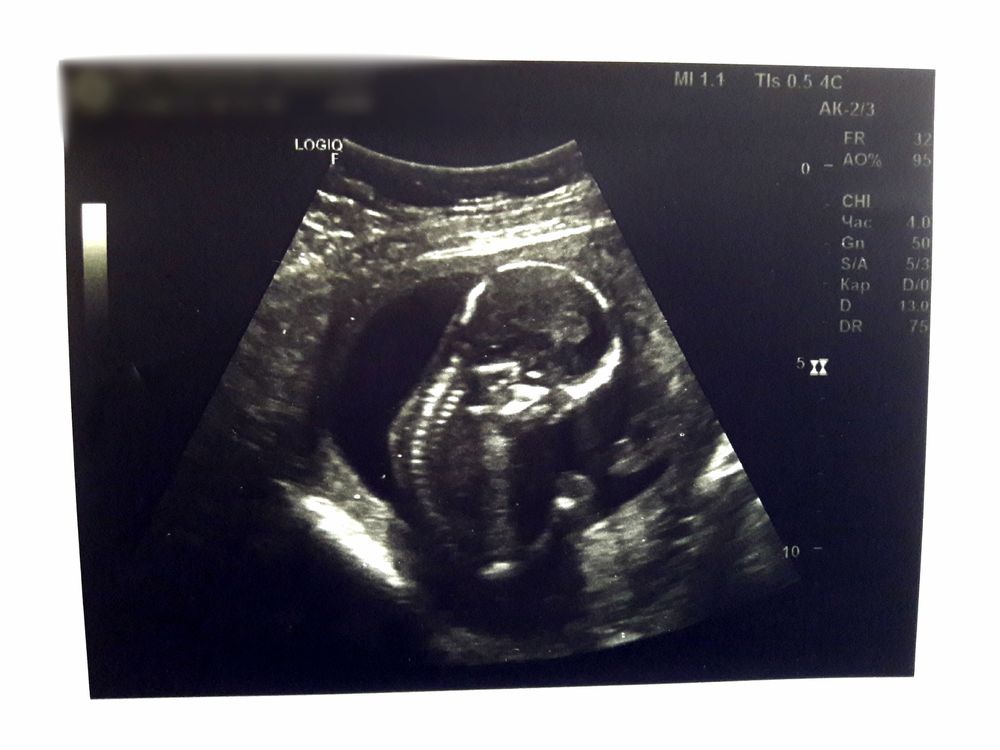

Затем 1 скрининг на котором нам говорят мы опережаем сроки и предпологают пол 60% на то что будет мальчик и 40% что будет девочка: